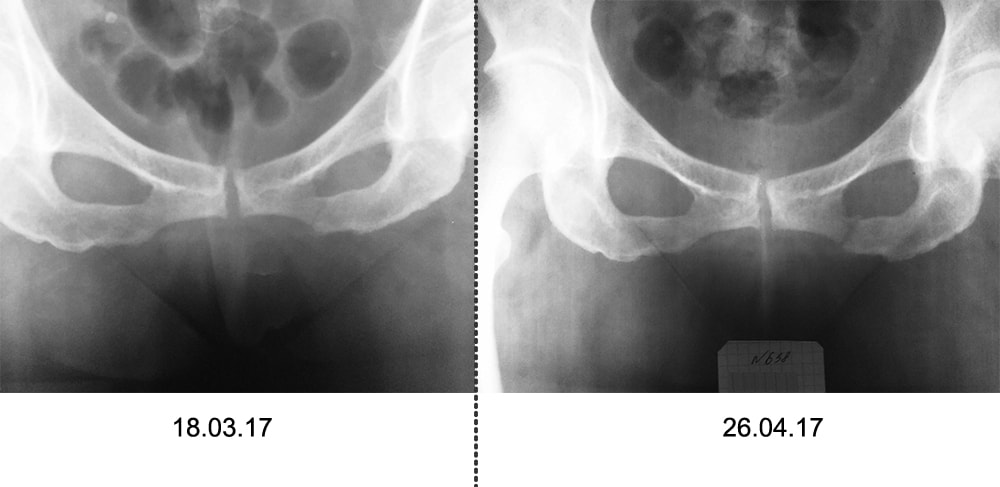

Женщина, 59 лет, после ДТП (10 марта 2017). Перелом нижней ветви седалищной кости.

Контрольный снимок сделали сегодня (26 апреля 2017)Меня не отпускает чувство, что там есть смещение лонной кости, которое не видно на снимке. Снимки для сравнения в приложении.

Снимки в разных проекциях, поэтому и видно не одинаково. Смещения большого нет, и, похоже, положение не изменилось. Таз надо оценивать не по таким огрызкам, а по снимкам таза целиком, и не только в фасной проекции, а и inlet и outlet.